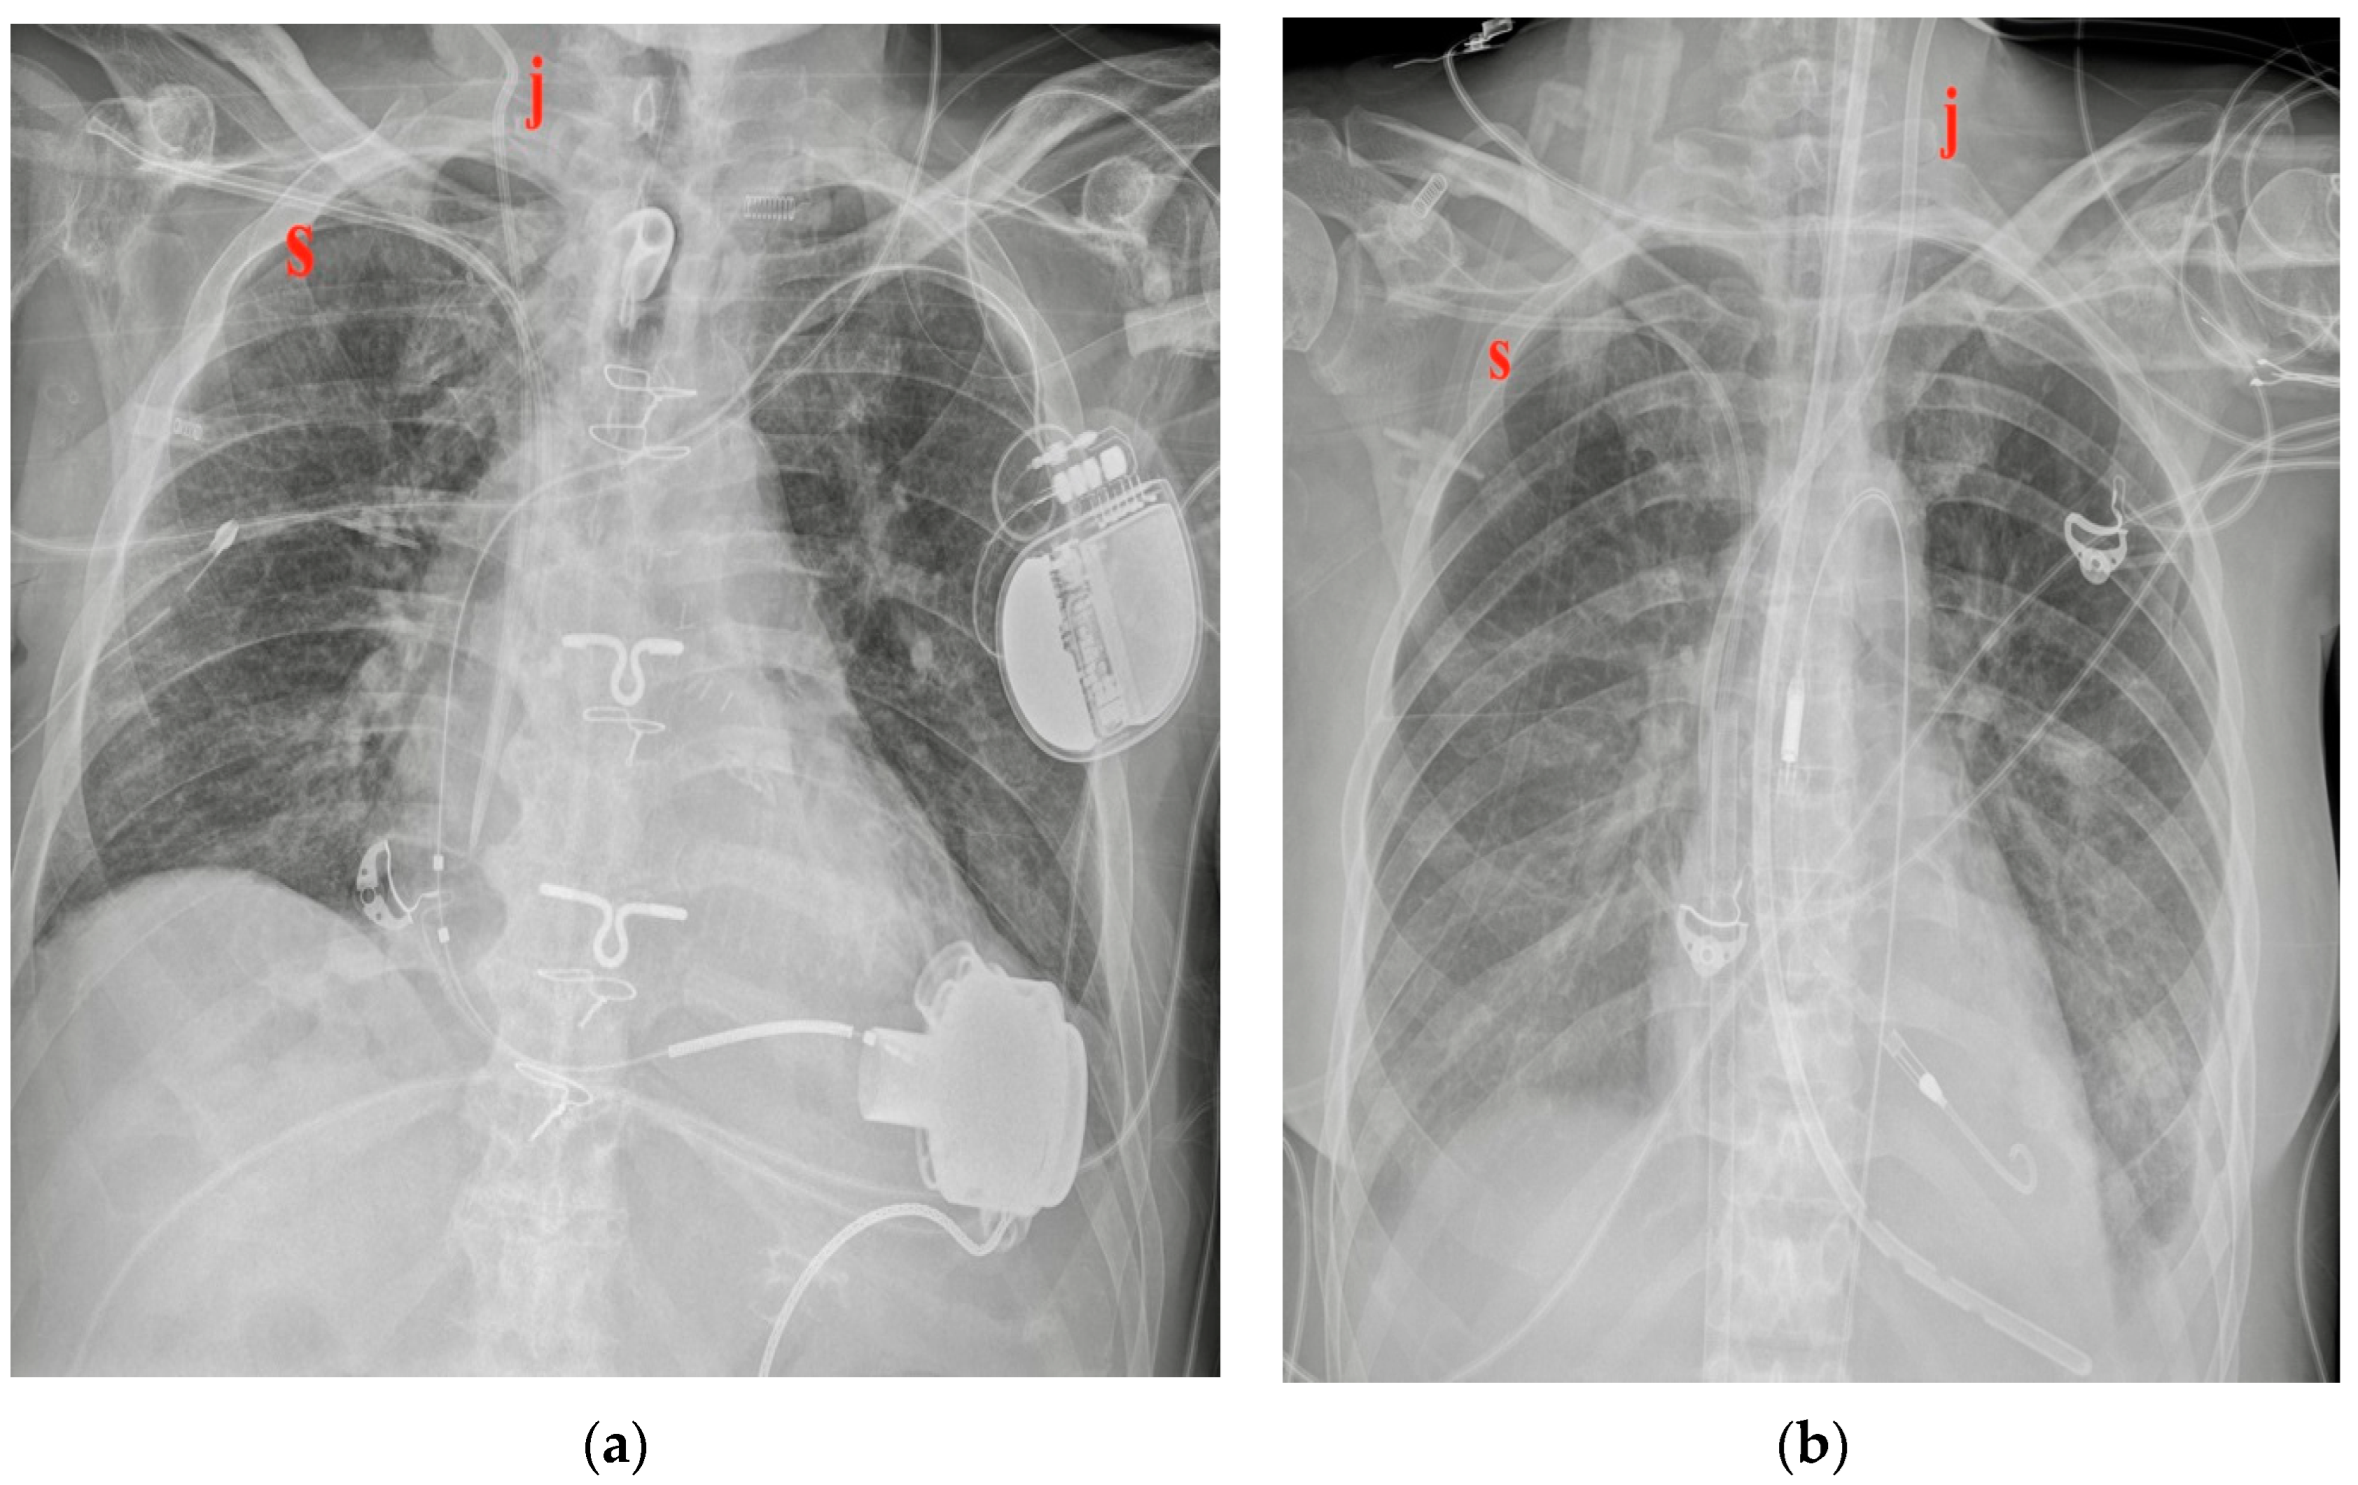

Figure 2.

Two different CVC insertion points. (a) Right jugular CVC (marked “j”) seen as arising from the neck of the patient, together with a right subclavian CVC (marked “s” in red); note that the two tips of the catheters tend to overlap. (b) Subclavian right CVC (“s” in red) and a left jugular CVC (“j” in red).